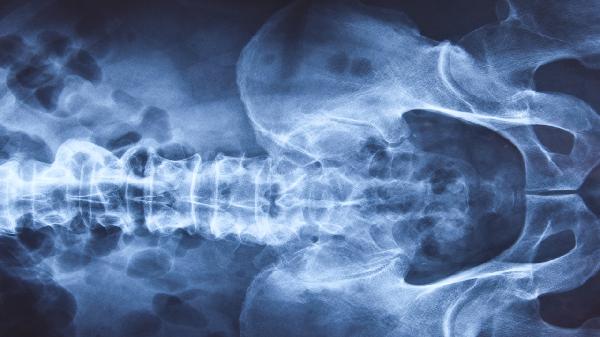

做CT需要空腹和憋尿吗 做CT检查注意事项盘点

做CT是否需要空腹和憋尿需根据检查部位决定。腹部CT通常需要空腹,盆腔CT可能需要憋尿,其他部位如头部、四肢等一般无须特殊准备。CT检查注意事项主要有检查前去除金属物品、告知医生过敏史和妊娠情况、配合体位保持静止等。